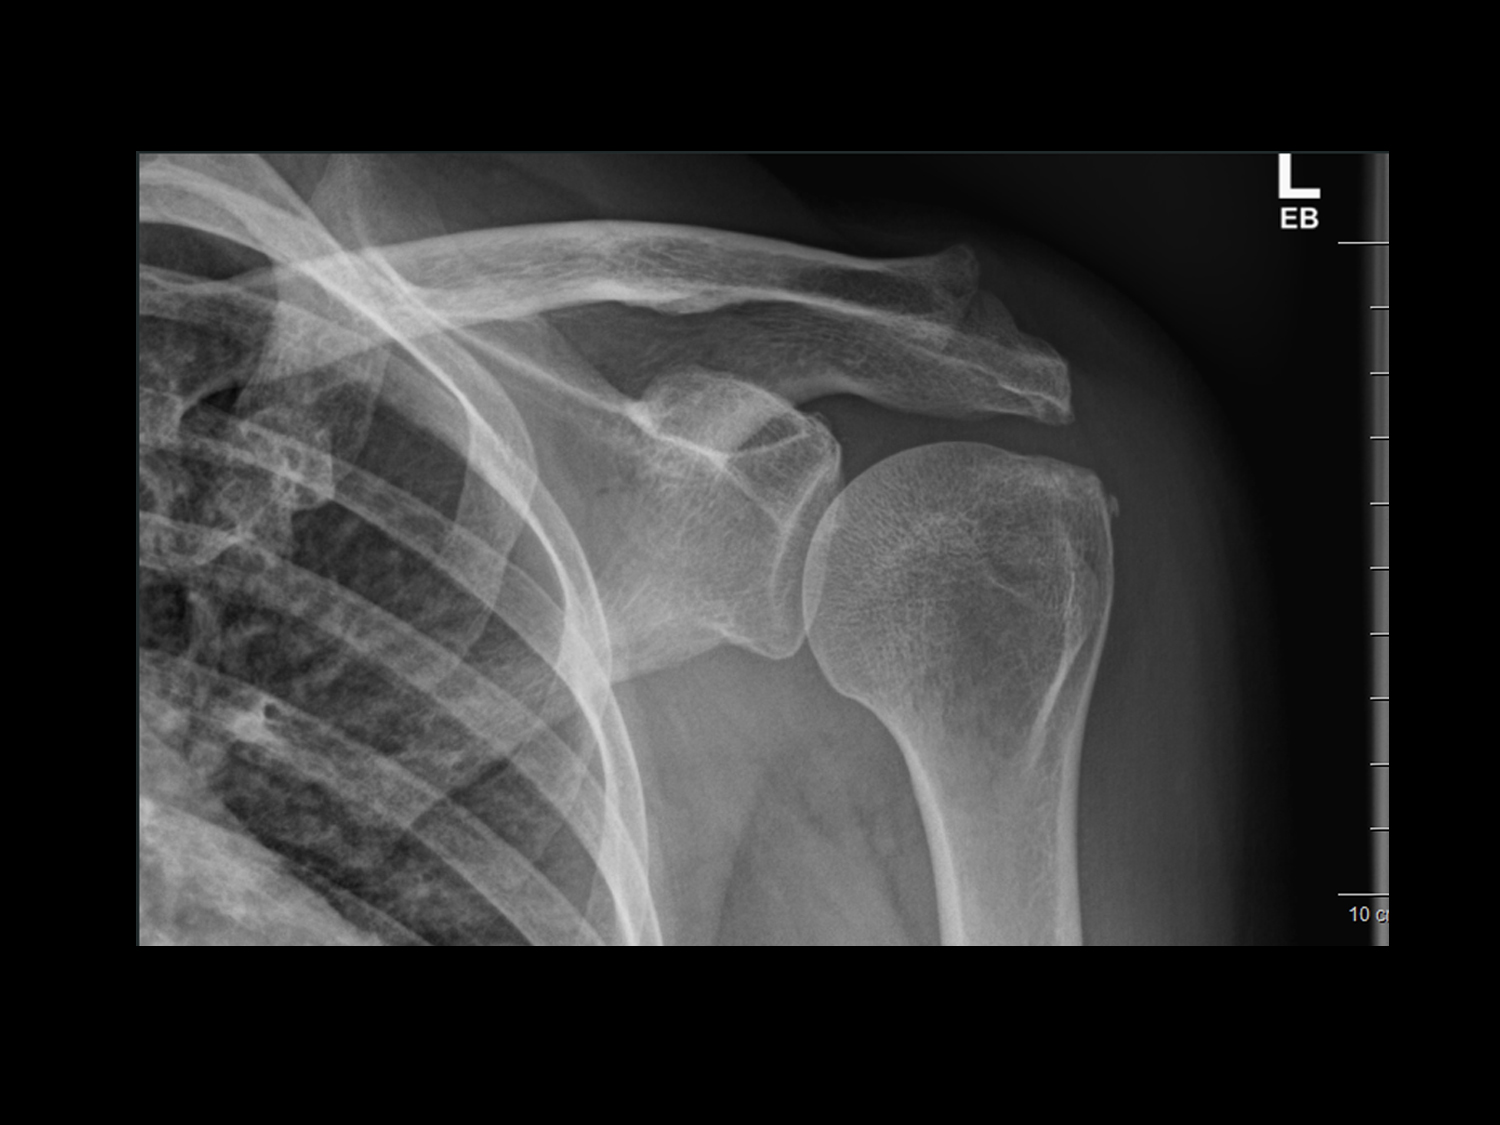

Röntgenuntersuchungen werden für eine Vielzahl von Zwecken eingesetzt, darunter die Diagnose von Knochenbrüchen, die Beurteilung von Organen wie Lunge, Herz und Verdauungstrakt sowie die Untersuchung von Weichteilgewebe auf Anzeichen von Verletzungen oder Erkrankungen. Die Röntgenbildgebung ist schnell, schmerzlos und nicht-invasiv und ermöglicht uns eine schnelle Diagnose und Behandlungsplanung.

Jedoch muss der Nutzen, der sich für den Patienten aus der Röntgendiagnostik ergibt, gegenüber dem der Strahlenexposition abgewogen werden. Das ist der Fall, wenn mit dieser Untersuchungsmethode die diagnostische Fragestellung beantwortet werden kann und kein alternatives Verfahren zu Verfügung steht. Zum Beispiel ist zu sicheren Diagnose und Therapieplanung eines Knochenbruches eine Röntgenaufnahme notwendig. Nach einer Operation sind Röntgenaufnahmen zur Material- und Lagekontrolle erforderlich.